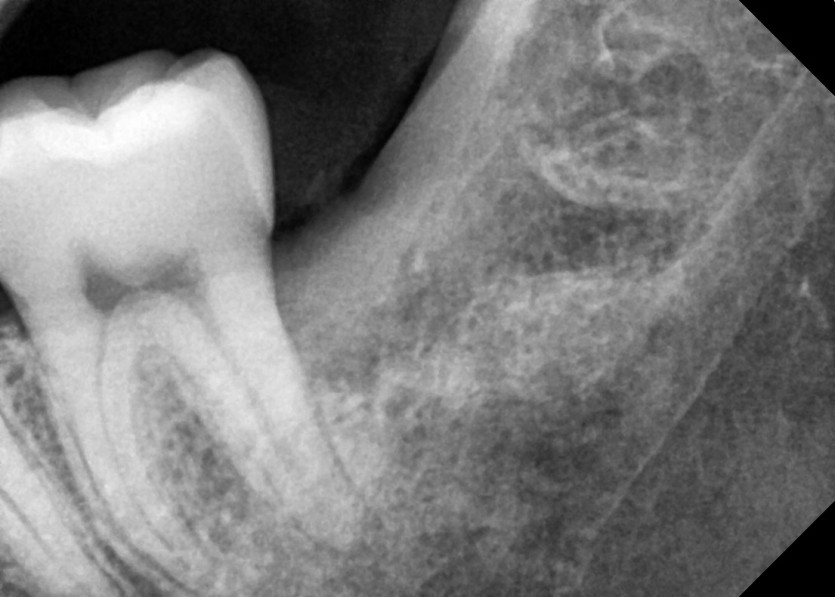

#28,38 사랑니 발치

구강 외과 전문의가 당일 발치했습니다.